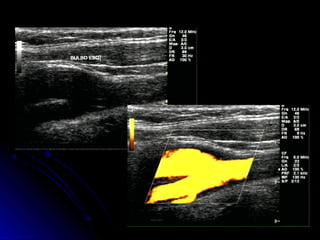

Power Doppler / Doppler ColorPower Doppler / Doppler Color

Melhor delimitação de placasMelhor delimitação de placas

TortuosidadesTortuosidades

Oclusão x Quase oclusãoOclusão x Quase oclusão